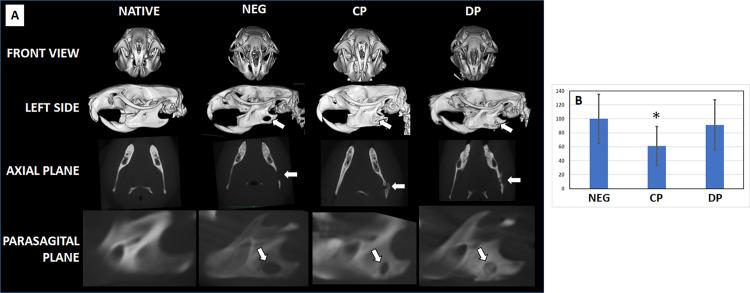

Regeneration of maxillofacial bone structures is challenging. One strategy for bone damage repair involves using bone filler particles. This study analyzed the regenerative potential of deproteinized bone particles (DP) and collagen-based bone particles (CP) to determine the effectiveness of each biomaterial in bone repair. Structural analysis using scanning electron microscopy and 3D scanning showed that DP and CP were structurally similar, comprising a heterogeneous mixture of bone particles of varying sizes and shapes. Ex vivo analyses, including morphological evaluation, LIVE & DEAD assays, and DNA quantification, demonstrated high biocompatibility of CP and DP with human cells in both direct and indirect contact at 24, 48, and 72 hours. Both particles were grafted onto Wistar rats with a critical mandibular defect for two months. Computed tomography revealed significant defect reduction in the CP group, but not in the DP group, compared to negative controls without any bone particles. Histological analysis showed biocompatibility of both particles in vivo and identified regenerative tissue with collagen fibers and mineralized spots in CP and DP, with more mineralized spots in DP. Histochemistry and immunohistochemistry confirmed collagen, proteoglycans, and osteocalcin presence in the regeneration area of CP and DP. These results confirm the biocompatibility and potential of both particle types for maxillofacial bone regeneration, particularly CP. Future studies should assess their clinical usefulness for patients with cleft palate, mandibular damage, and other maxillofacial applications involving tissue engineering techniques.